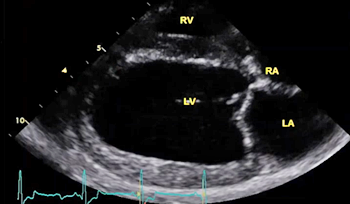

(In the image at right, the red spurt of blood is shooting upward and backward, from the left ventricle, through the not-fully-closed mitral valve, back into the left atrium.)

The echocardiograph examination shows the dimensions of the heart chambers, wall thickness and movement, valve movement and lesions, fractional shortening, among other characteristics. The echo screen shows the amount of wall contraction, which enables the operator to determine contractility, preload*, and afterload*. These factors are used to calculate "fractional shortening" (FS%) which is used as an indication of ventricular performance and of myocardial contractility.

• enlargement of the heart's left side

As noted above, what is not visible outwardly, before the dog reaches heart failure, is enlargement of the left chambers of the heart. As greater quantities of blood leak through the damaged mitral valve from the left ventricle back into the left atrium, the thin-walled atrium gradually begins to swell and enlarge (see x-ray image of a severely enlarged left atrium, outlined in red, above) -- called remodeling or cardiomegaly or dilation -- to accommodate the overload of blood, and there is a reduction in the ability of the left ventricle to provide sufficient blood to meet the demands of the rest of the body. The heart then has to pump harder and faster, to meet those demands. The shut-down of the distant blood vessels also has the effect of causing the left ventricle to beat against a higher resistance, causing another increase in mitral valve leakage.